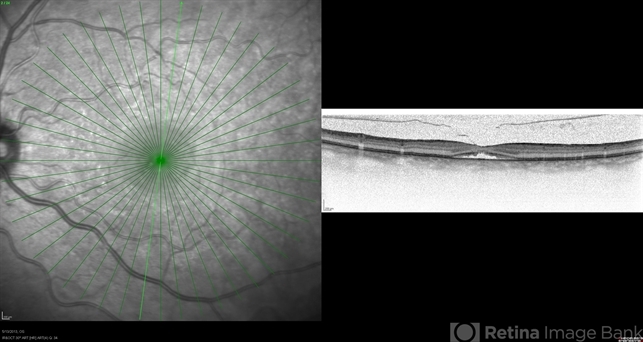

- macular hole, optical coherence tomography (OCT)

- 5 weeks post-op JETREA for stage 2 MH. OCT shows closing macular hole, but the cortex still attached.